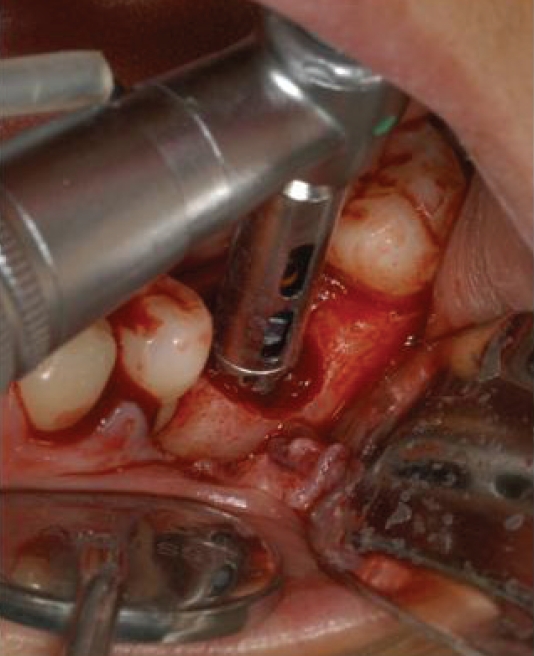

2005년까지는 국민건강보험요양급여의기준에 관한 규칙에서 치아의 보철치료(보철재료 및 기공료등 포함)는 비급여대상으로하고 있으며 보철의 범주에 속하는 임프란트 또한 비급여 대상으로, 임프란트시술 후 이와 직접 연관된 합병증 및 후유증 치료는 비급여토록 하였다. 2005년 5월 11일 진료평가심의위원회는 임프란트 치료시 최종철물을 장착하고 6개월이 경과한 후 발생한 임프란트 주위염, 임프란트 동요 및 파절 등은 이와 직접적인 진료로 보기 곤란하므로 요양급여로 인정키로 함으로서 한동안은 임프란트 주위염, 임프란트 동요 및 파절(Fig. 1) 등 3가지 경우에 한하여 기존의 건강보함항목을 적용받을 수 있는 근거가 마련되었다.

Fig. 1.

임플란트 파절

jkda-2026-64-2-006f1.jpg